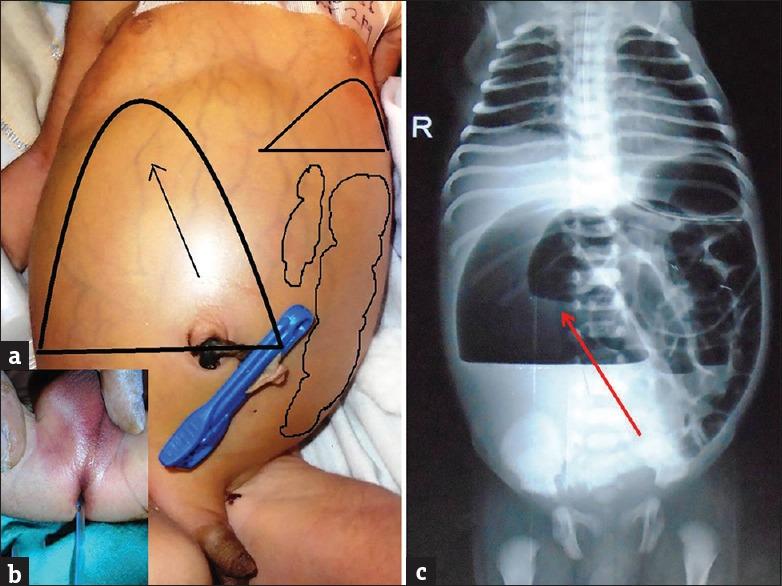

We are adding two cases of congenital pouch colon with rectal atresia (RA) to the already published five cases. The presentation of RA is often delayed owing to the presence of normal anus, however, clinical evaluation, plain abdominal radiograph, and urine examination for meconuria, may help in detecting this rare association early.